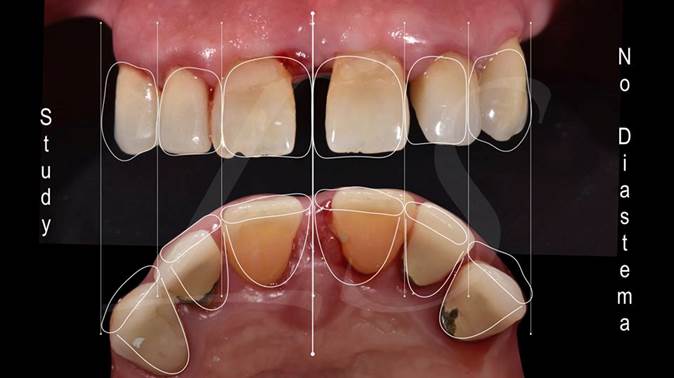

Clinical case: Full-arch implant treatment with immediate loading & extraction implantation

- Courtesy of Dr. Laurent Sers, France -

AnyRidge, R2GATE, guided surgery, Dr. Laurent Sers, immediate loading, maxilla

AnyRidge implant system, R2GATE, Digital prosthesis